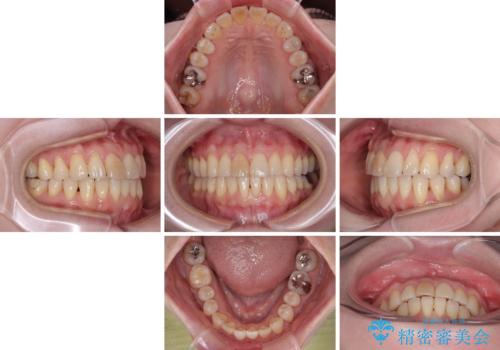

前歯のデコボコをインビザライン・モデレートで矯正治療

- 上下前歯のデコボコを気にして来院された患者様です。

安価なインビザラインパッケージを用いての治療を希望されており、デコボコの程度が中等度であったため、インビザライン・モデレートを用いて矯正治療を行うこととしました。

インビザライン・モデレートは、製作できるアライナーの枚数に制限があるため、移動可能な量に限りがあるものの、インビザライン・ライトよりも枚数が多いため、幅広い症例に対応可能です。